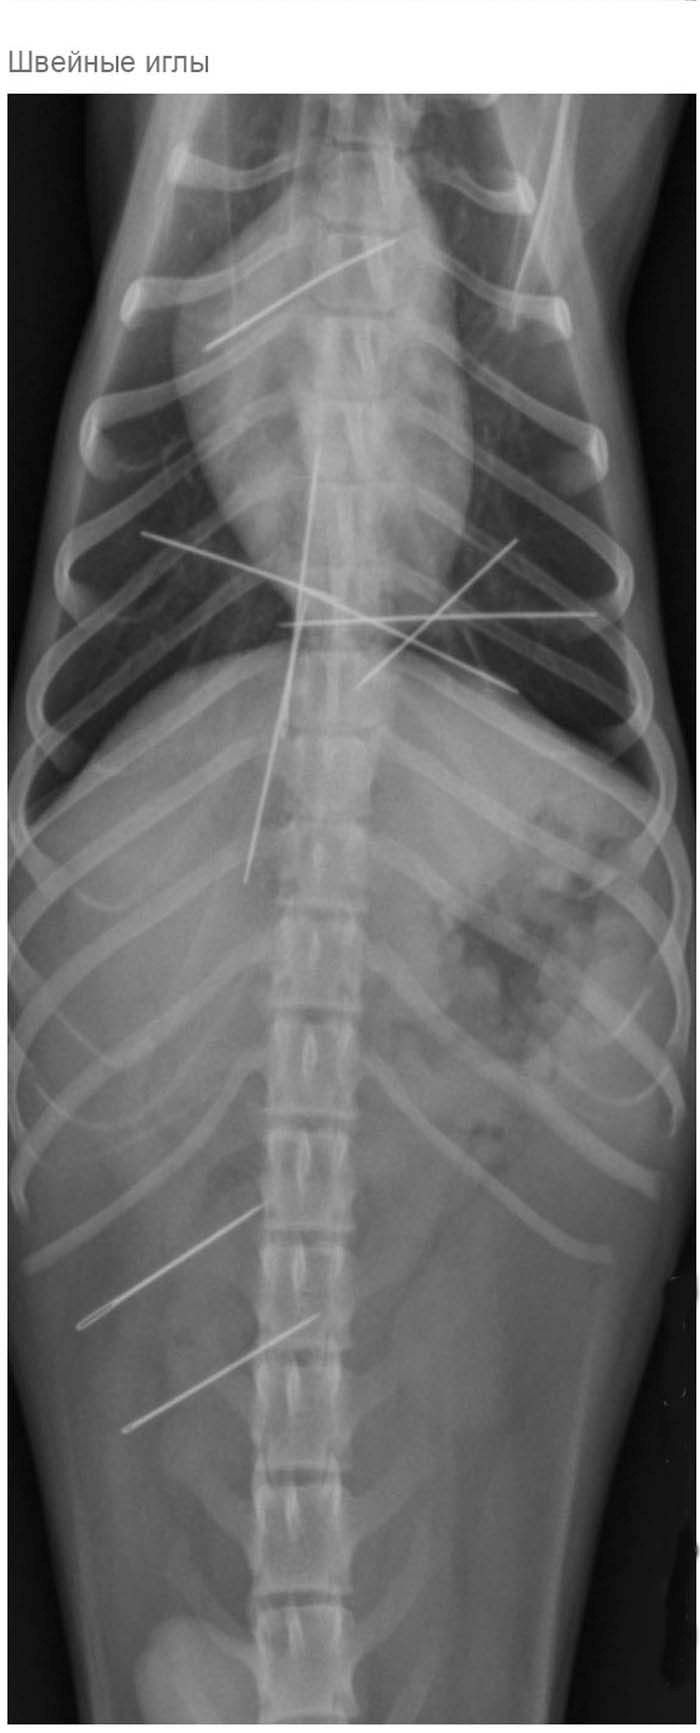

» Что может оказаться в желудке собаки

Что может оказаться в желудке собаки